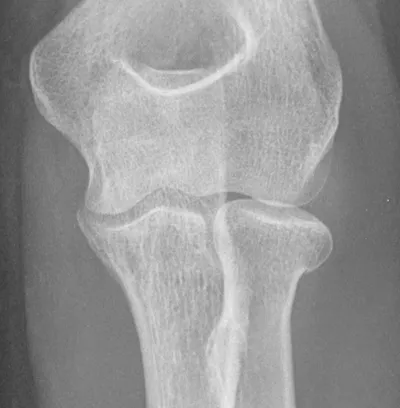

Sail sign of elbow effusions

Elbow

4/10/2026